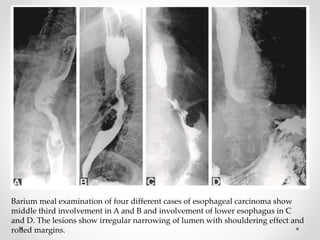

Barium meal examination of four different cases of esophageal carcinoma show

middle third involvement in A and B and involvement of lower esophagus in C

and D. The lesions show irregular narrowing of lumen with shouldering effect and

rolled margins.

Barium meal examinationof four different cases of esophageal carcinoma show middle third involvement in A and B and involvement of lower esophagus in C and D. The lesions show irregular narrowing of lumen with shouldering effect and rolled margins.